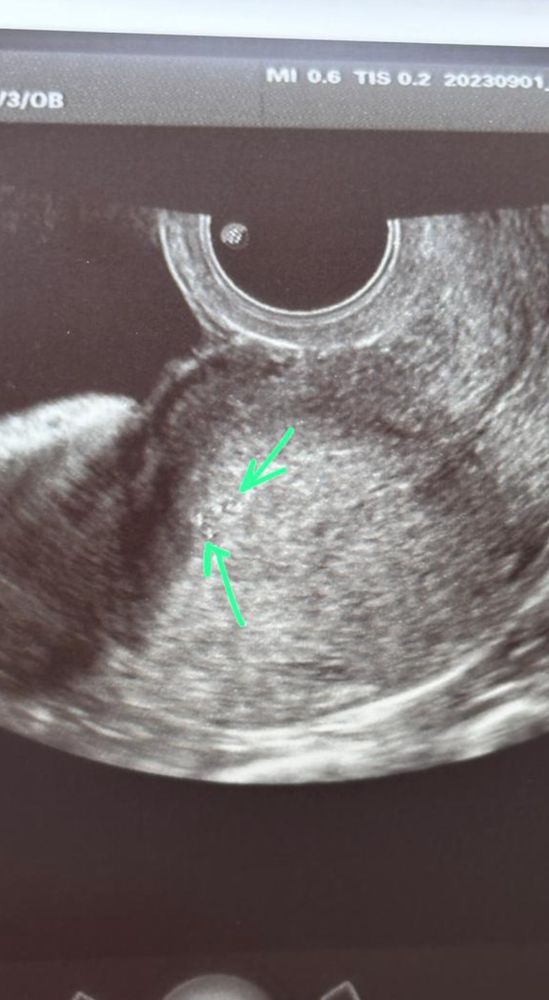

Ангелина, мне назначили кардиомагнил и 4 капельницы с ИГ до переноса. Посмотрим по результатам следующего переноса, сработает ли. Вот АФС врачом из Лапино написано) Изображение

Мария Андреева, последний результат хгч 79, не 790 я сама была удивлена, что что-то было видно, у меня просто глаза на лоб вылезли! ну рассказываю как есть.

Eco_do_pobedy, это какой дпп был? По узи больше похоже на остаток капли от среды. Пя не так выглядит, оно чёрное. А вот белое как раз капля от среды. Она до двух недель может быть в матке

Ангелина, не знаю, передаю то, что мне говорили квалифицированные люди в этой отрасли)) может это и капля среды, но их две и был рост хгч)) так что точно остатки от двух эмбриошек. По дпп точно не помню, наверно типа 14, я тогда уже отменила поддержку и пошла на УЗИ в принципе по другому органу, просто попросила посмотреть, что в матке, так как никак не начинались месячные

Eco_do_pobedy, ну два эмбриона соответственно две капли. Просто увидеть пя можно только с хгч не ниже 800, ну если супер пупер аппарат то 600. Жаль что вам врачи втирали эту версию. Извините за сленг, но это так и есть. Тоесть хгч вы сдавать до узи, или в тот день когда узи было?

Eco_do_pobedy, при хгч 79 пя разглядеть не возможно. Ну и фото тоже не убеждает меня. Пя оно по крупнее. Я 12 лет проверялась. И мутации фолатного цикла и hla, и киллеры и антитела к хгч, и даже синдром виллебранта, и пайпель-биопсия, лапара, 2 гистеры и тд до бесконечности. Но кстати, ещё есть обследования, которые не сдавали мы. Но если что-то находят, то этот артефакт не обязательно является причиной бесплодия. А пгд Вы делали? И возраст у Вас какой?

Мария Андреева, ну вот УЗИ есть, оно мое. Что врач УЗИ, что мой РЕ подтвердили, что это подсаженные эмбрионы. У РЕ в карте есть фото матки до подсадки. В первый протокол мы делали ПГД всех 5 эмбрионов, только один не прошел его, и как нам сказал генетик, это случайная поломка, не завтсящая от возраста и нашего кариотипа. Кариотипы у нас хорошие, мне 28 лет, мужу 39. Во втором протоколе не делали ПГД, потому что получилось всего двое и этих двоих в свежем и подсадили. Сейчас у меня 3 стимуляция и будем все делать как в прошлый раз, только подсаживать одного в свежем, другие в крио уйдут. Подключим ИГ и плаквенил я уже пью